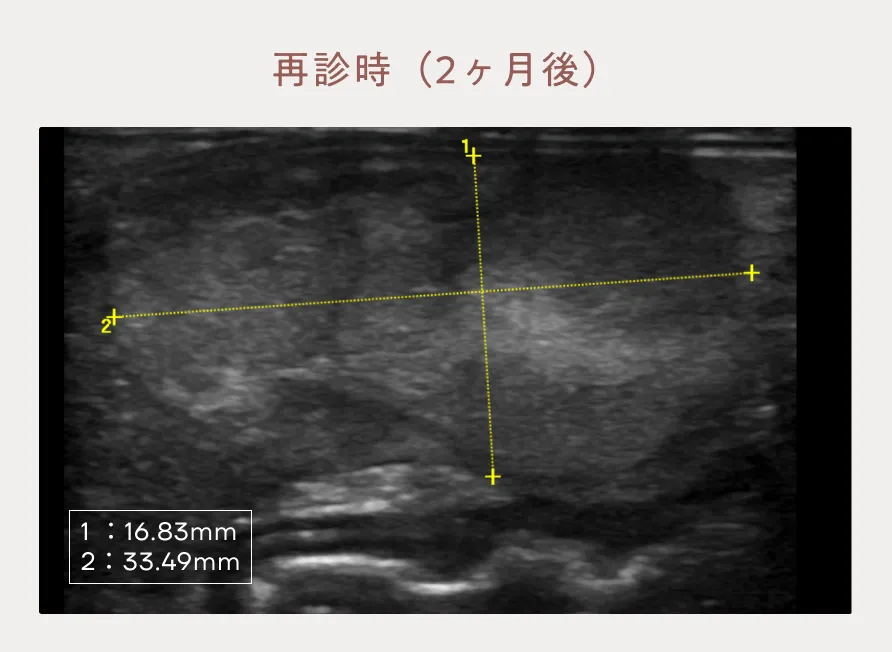

初診から2ヶ月経過したところで肝臓腫瘤に対して腹部超音波検査を実施したところ、左肝区域腫瘤は増大(16×33mm)しており、内部構造はより不整で、境界明瞭に変化していました。中央肝区域の結節に変化はありませんでした。時間経過による画像所見の変化を踏まえ、左肝区域腫瘤は肝臓の悪性腫瘍(肝細胞癌)の可能性が高いと暫定診断いたしました。ご家族には改めて2次診療施設でのCT 検査や外科手術についてご提案しましたが、余生は無理なく過ごすことを選択されました。本疾患だった場合に将来的にどうなるのかご説明をし、無治療で余生を過ごしていただくことになりました。